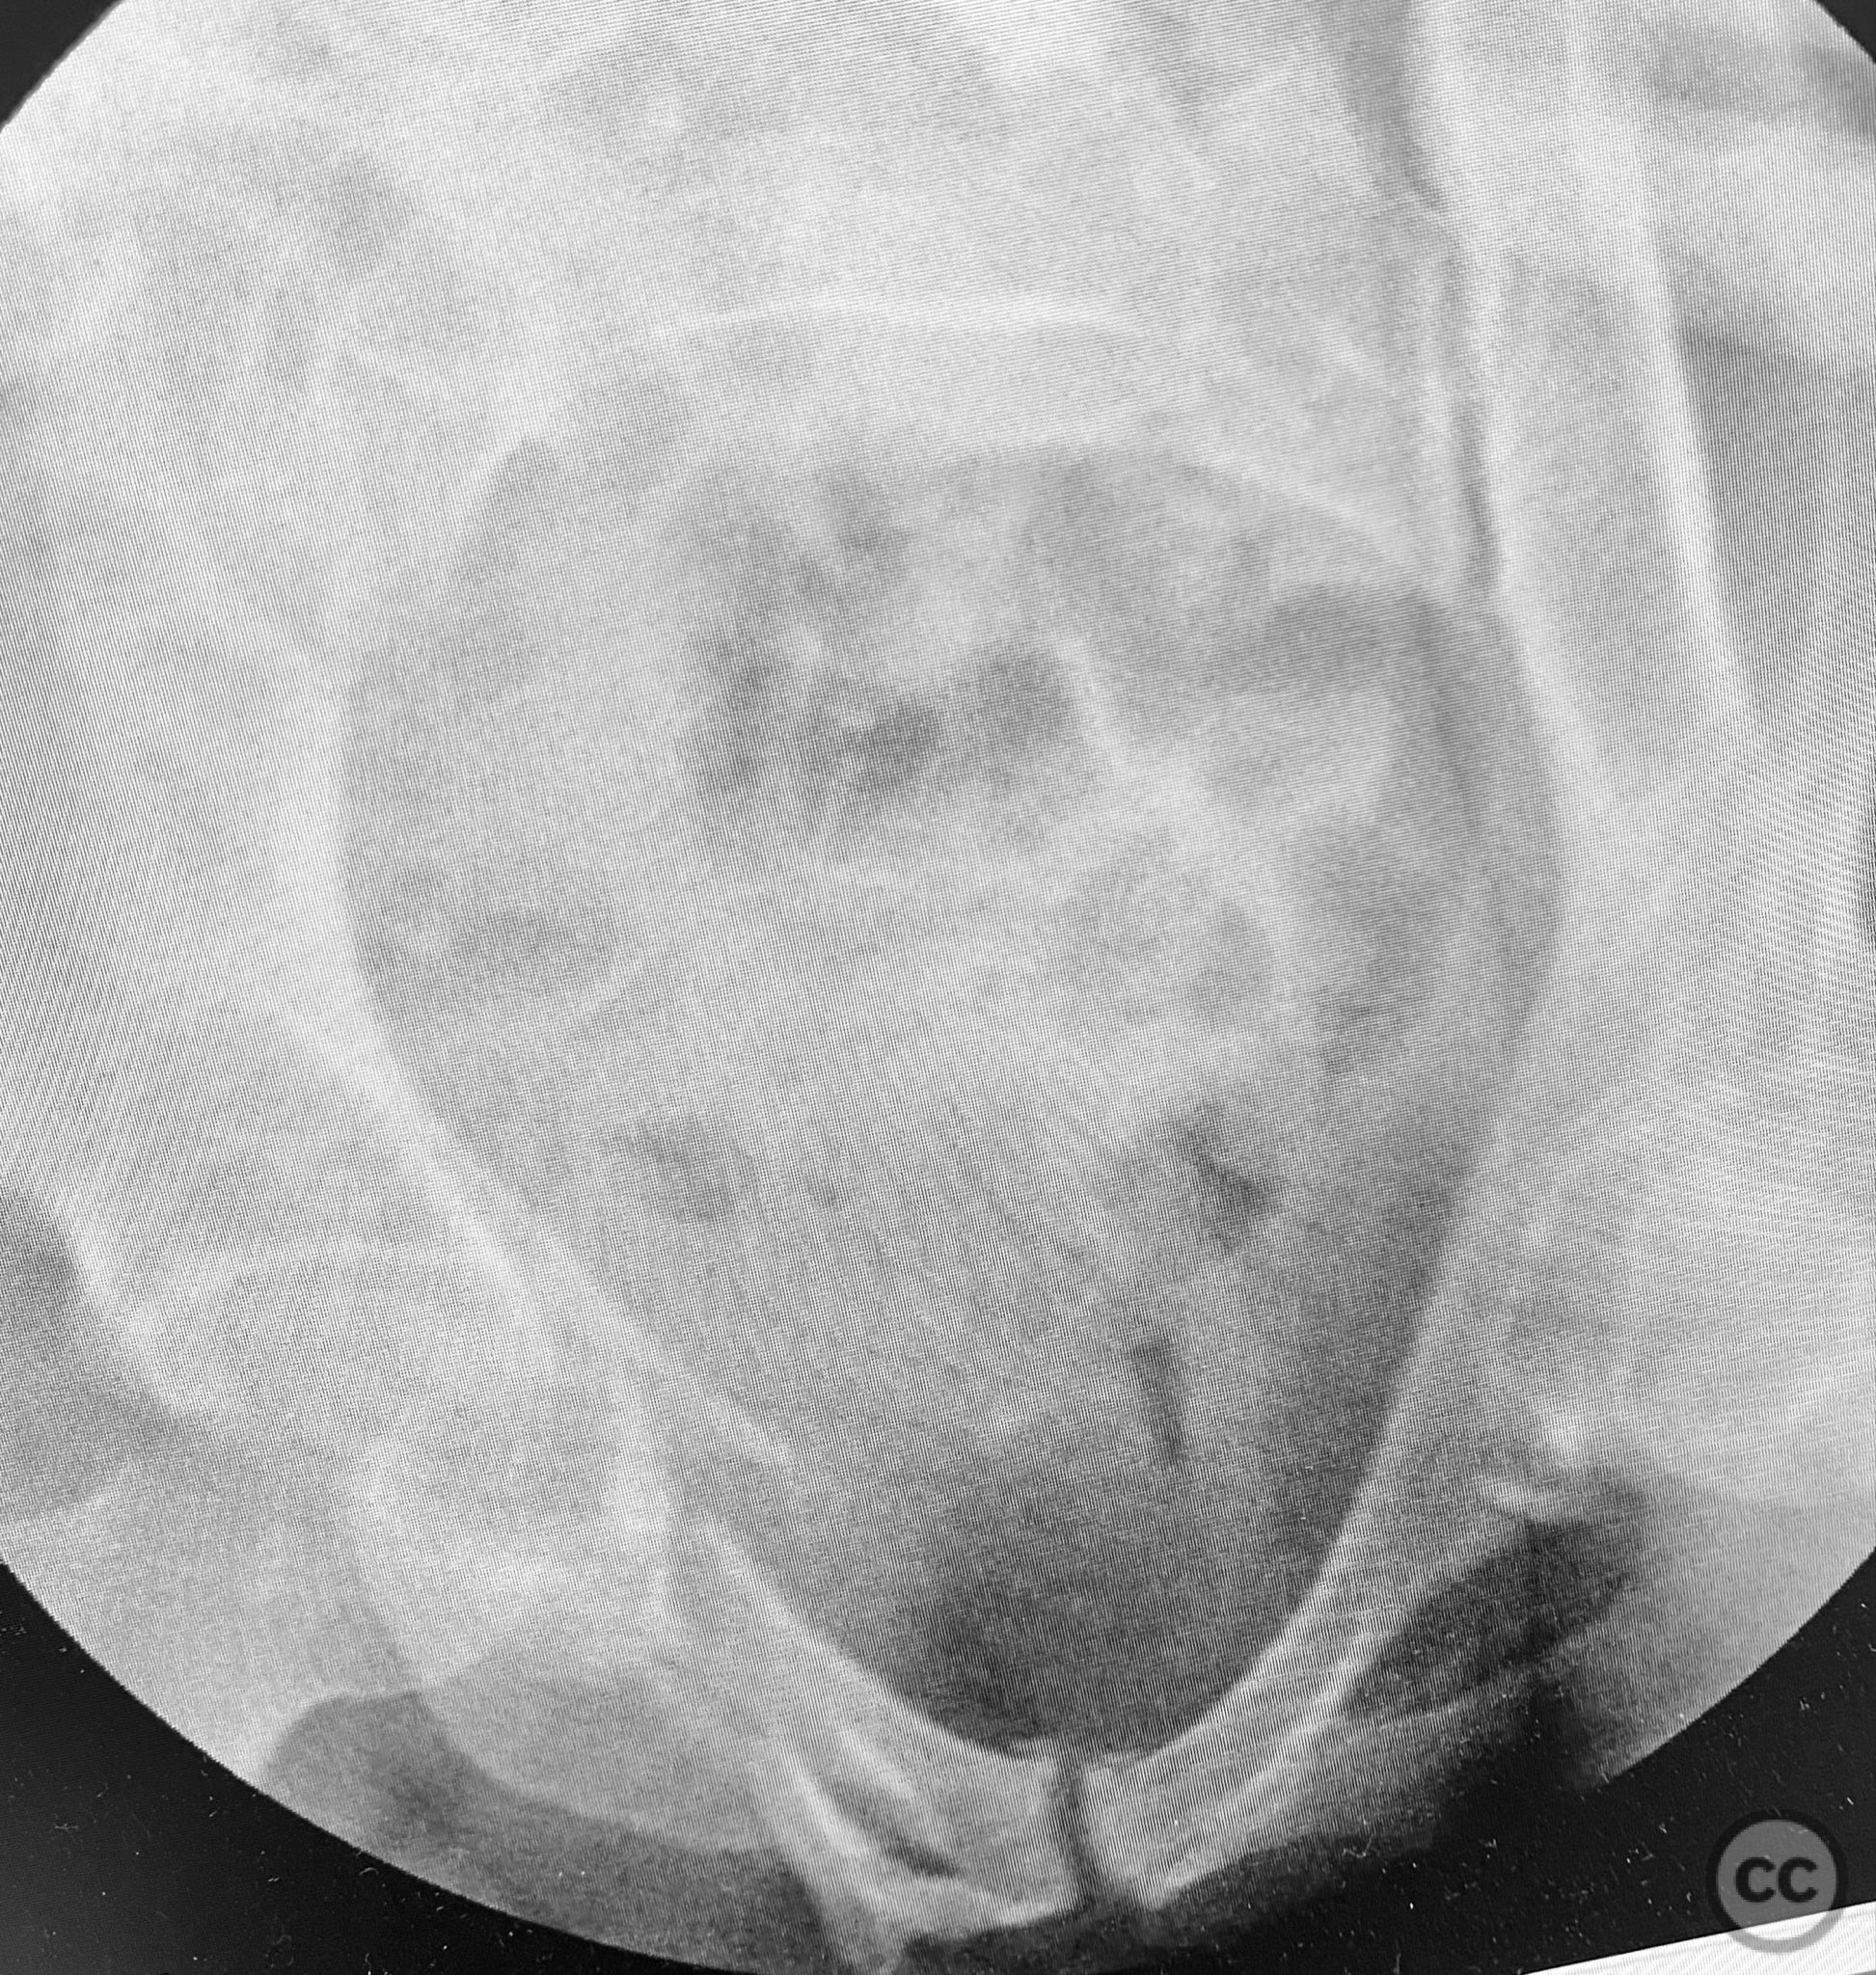

Planning remarks:  The preoperative plan was to assess pelvic stability under anesthesia, utilizing manual compression of the cristae iliacae with intraoperative fluoroscopic inlet imaging to identify sites of instability. Percutaneous screw fixation was planned for unstable zones, with reduction refined as necessary under imaging guidance.

Intraoperative assessment confirmed instability at the posterior pelvic ring with manual stress testing under fluoroscopy. Reduction was achieved with gentle manipulation and maintained during percutaneous screw insertion. The use of intraoperative inlet and outlet views was critical for accurate screw placement and confirmation of reduction. The minimally invasive technique minimized additional soft tissue trauma in this polytrauma patient.